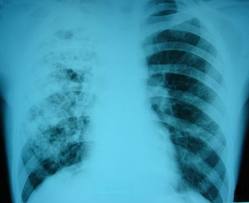

У березні відзначають Міжнародний день боротьби з туберкульозом. Фахівці застерігають: сьогодні кожен у групі ризику. Найскладніше, як виявляється, помітити хворобу на ранній стадії. Водночас найпростіший метод профілактики — проходити флюорографію один раз на 2 роки, а ще — добре харчуватися.